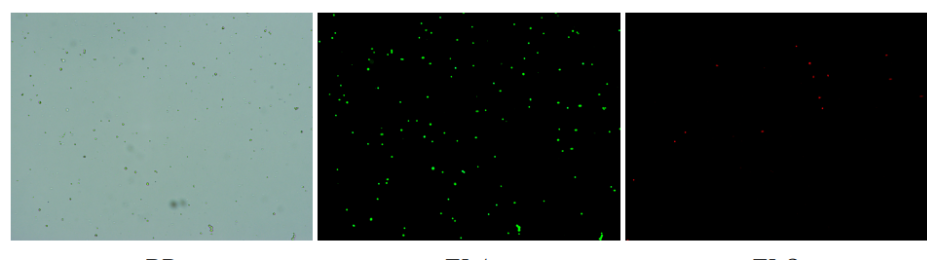

肝臟是人體代謝和解讀的器官,在體內(nèi)發(fā)揮氧化、儲(chǔ)存肝糖、合成分泌性蛋白合成等,肝臟也制造消化系統(tǒng)中之膽汁,人肝約有25億個(gè)肝細(xì)胞。但是解離肝臟組織懸液并不簡(jiǎn)單,首先,肝臟代謝旺盛,離體后肝細(xì)胞無(wú)法進(jìn)行正常的有氧糖酵解,細(xì)胞活力會(huì)迅速下降,另外,肝細(xì)胞的線粒體很多,每個(gè)細(xì)胞大約有1000個(gè)左右,遍布于胞質(zhì)內(nèi)。因此,很難得到符合單細(xì)胞測(cè)序要求的單細(xì)胞懸液。百邁客生物在肝臟組織單細(xì)胞懸液制備方面有豐度的實(shí)操經(jīng)驗(yàn),開(kāi)發(fā)了獨(dú)有的解離體系,下面來(lái)看實(shí)驗(yàn)結(jié)果:

實(shí)驗(yàn)結(jié)果

人肝癌樣本,懸液背景干凈,活性91.69%,結(jié)團(tuán)率6%

人膽管癌樣本,活性90.45%,結(jié)團(tuán)率7.2%

Tips: 肝實(shí)質(zhì)細(xì)胞經(jīng)過(guò)解離后因?yàn)槿毖醴浅H菀装l(fā)生凋亡,導(dǎo)致占比很低,如果老師關(guān)注肝實(shí)質(zhì)細(xì)胞的話,建議采用單細(xì)胞核懸液的方法。